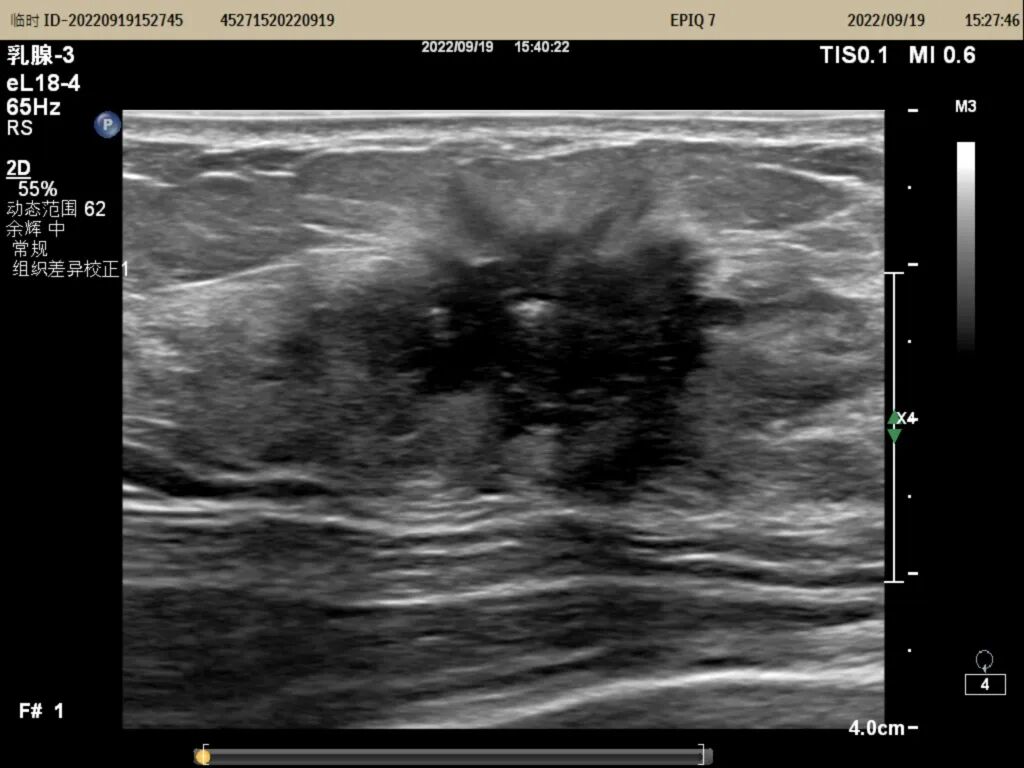

▲右侧乳腺肿物大小约23mm×19mm×21mm,BI-RADS分类:5类

▲实时穿刺图像

超声引导下乳腺穿刺活检就是用直径约1mm穿刺针在超声引导下穿入乳腺肿物内,取出病变组织进行病理检查明确诊断。只有确定了肿物的性质,才可以根据病理结果选择相对应的治疗方式,达到早诊断早治疗的目的。